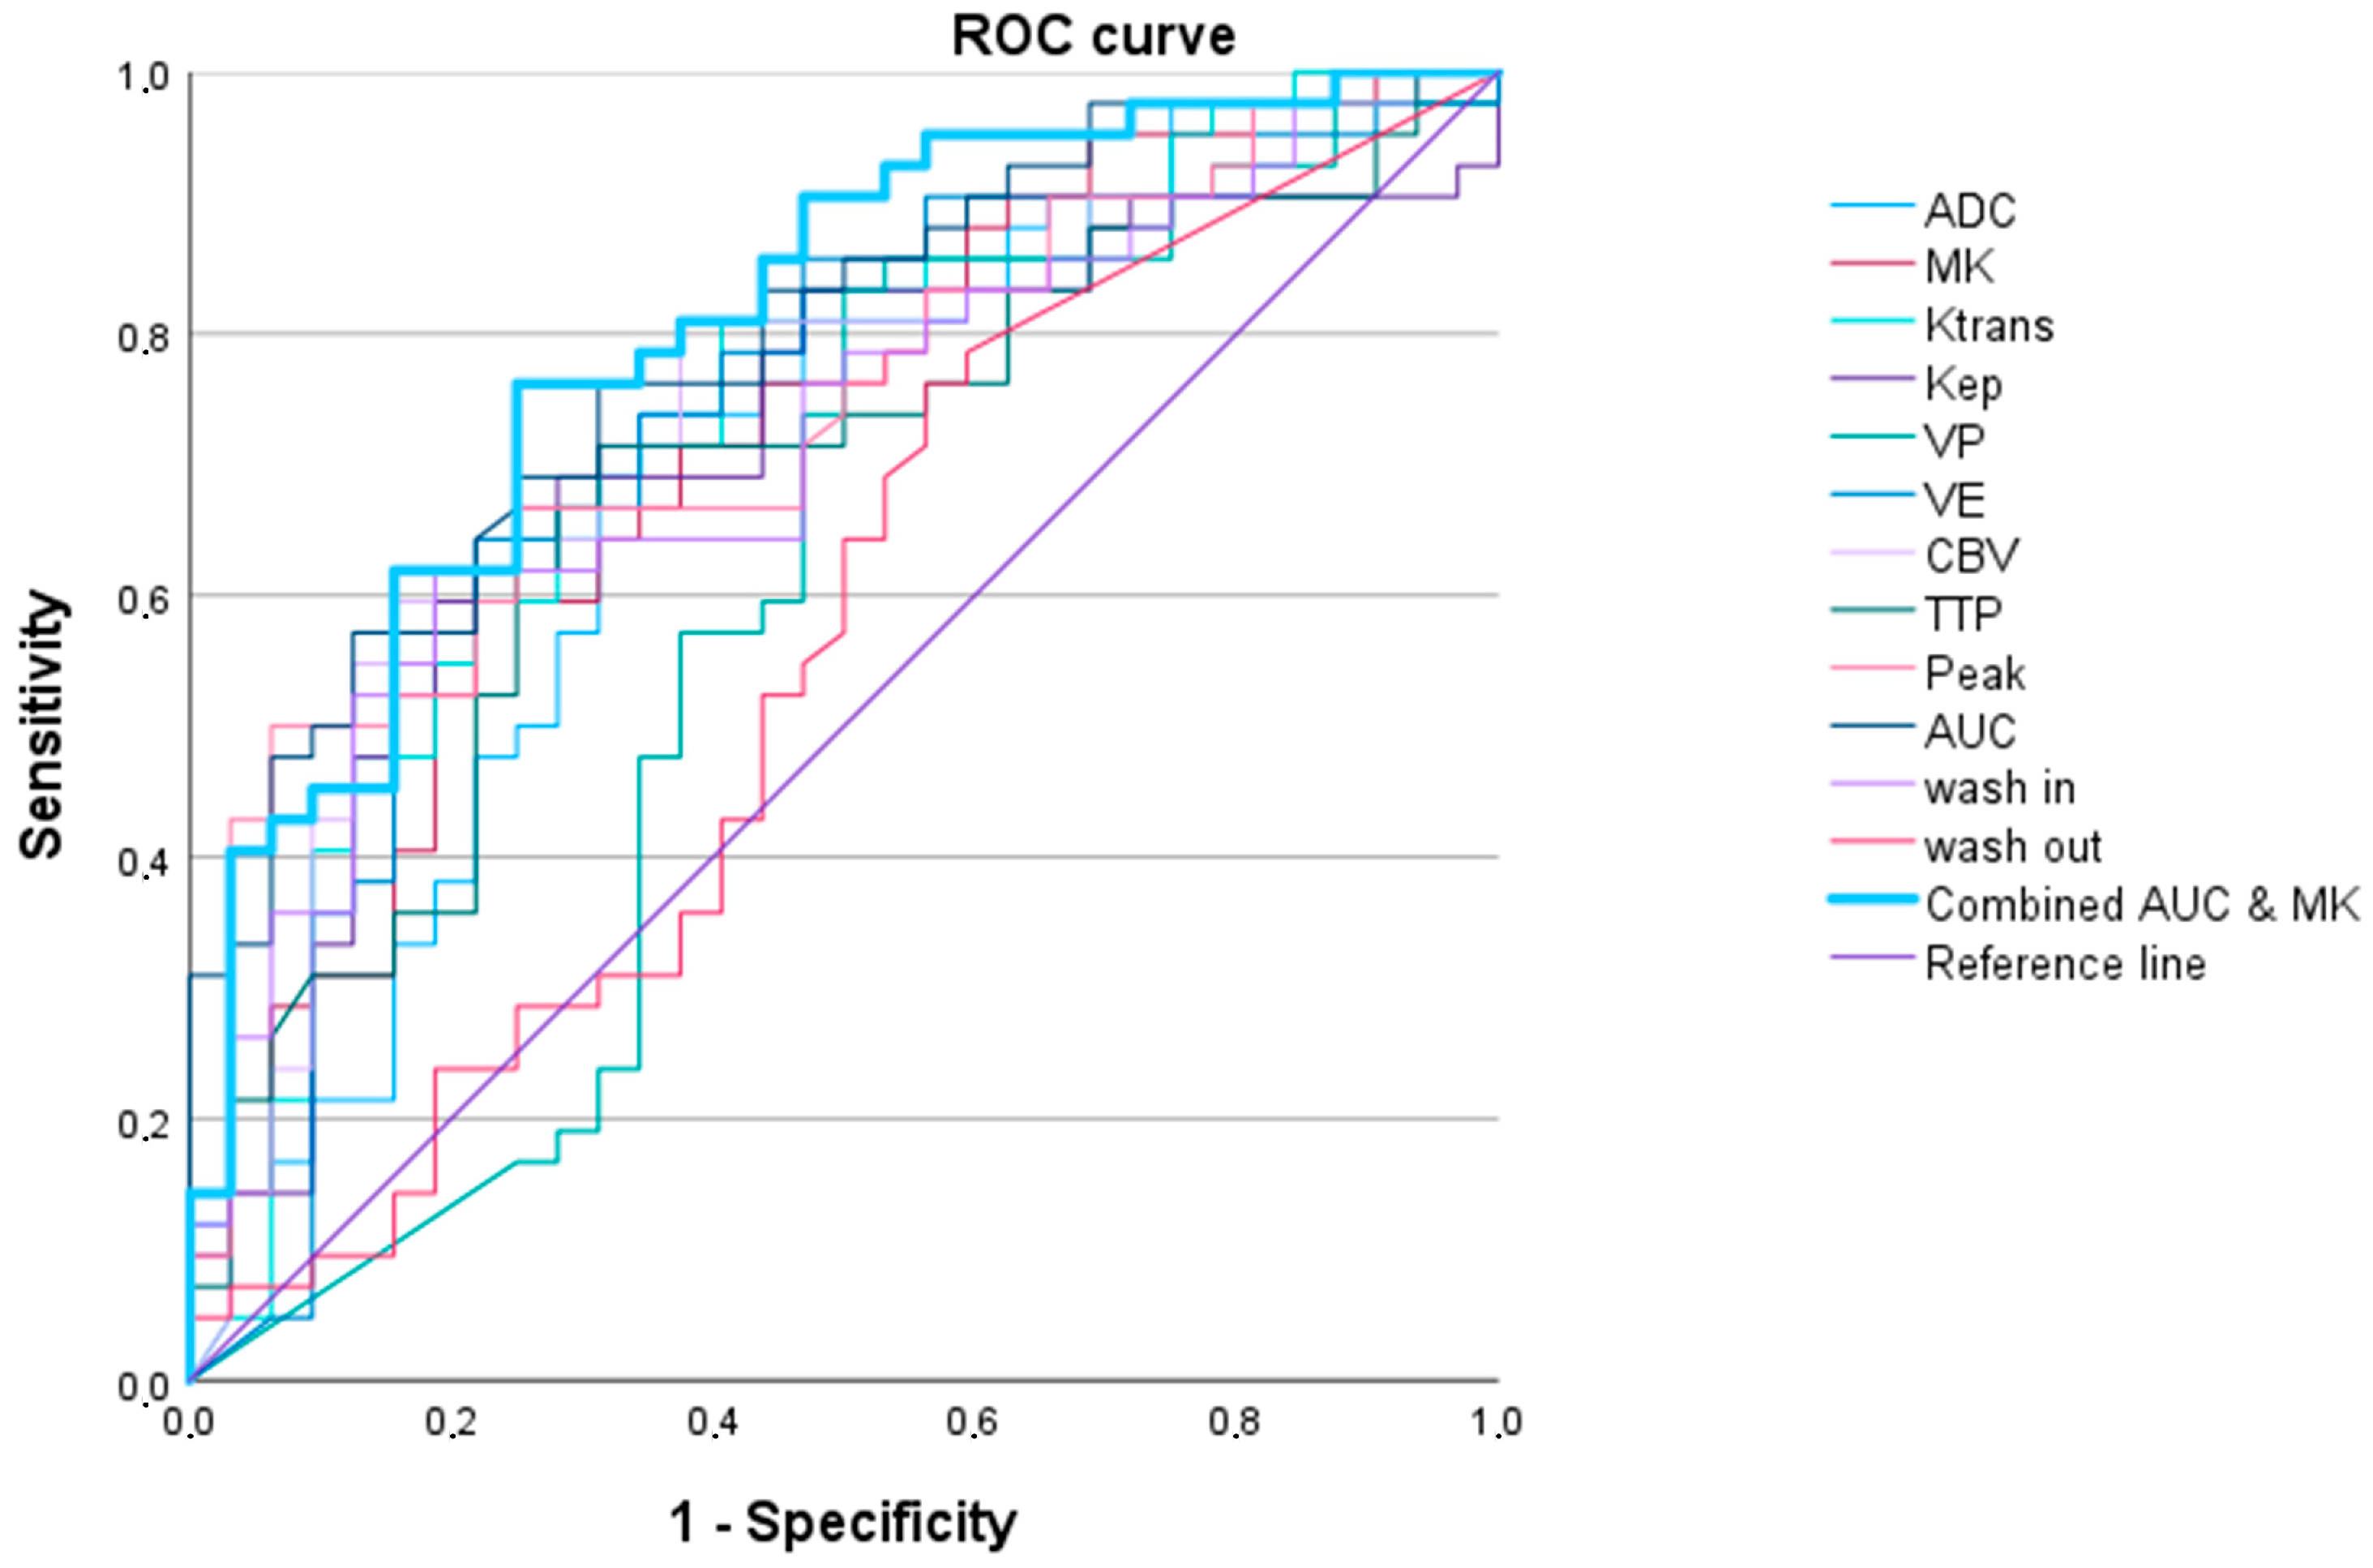

3.2.3. High-Grade Oligodendroglial versus High-Grade Astrocytic Gliomas

| Oligodendroglioma (IDH1/2 Mutated 1p/19q Codeletion) (WHO Grade 3) vs. Glioblastoma IDH1/2 Wildtype (WHO Grade 4) and Astrocytoma IDH1/2 Mutated (WHO Grades 3 and 4) | ||||||

|---|---|---|---|---|---|---|

| AUC (95% Confidence Interval) | p Value | Cut-Off Value 1 | Sensitivity | Specificity | AIC | |

| Ktrans | 0.739 (0.598–0.880) | 0.010 | 834.1 | 0.750 | 0.745 | 57.060 |

| Kep | 0.655 (0.471–0.838) | 0.095 | 1665.0 | 0.667 | 0.800 | 60.861 |

| Vp | 0.642 (0.490–0.795) | 0.124 | 1269.2 | 0.917 | 0.436 | 61.163 |

| Ve | 0.680 (0.505–0.855) | 0.052 | 134.7 | 0.667 | 0.836 | 62.006 |

| CBV | 0.720 (0.561–0.878) | 0.018 | 900.6 | 0.750 | 0.745 | 59.183 |

| TTP | 0.660 (0.473–0.847) | 0.085 | 669.4 | 0.667 | 0.782 | 60.728 |

| Peak | 0.733 (0.571–0.894) | 0.012 | 10.9 | 0.583 | 0.873 | 58.150 |

| AUCDCE | 0.721 (0.555–0.887) | 0.017 | 41.4 | 0.583 | 0.836 | 61.297 |

| wash in | 0.715 (0.587–0.843) | 0.020 | 471.6 | 0.750 | 0.727 | 57.818 |

| wash out | 0.433 (0.262–0.605) | 0.472 | 44.0 | 1.000 | 0.127 | 64.886 |

| ADC | 0.721 (0.555–0.887) | 0.054 | 505.4 | 0.583 | 0.836 | 60.645 |

| MK | 0.741 (0.592–0.890) | 0.009 | 658.3 | 0.750 | 0.655 | 57.369 |

| Ktrans and MK 2 | 0.806 (0.700–0.912) | <0.001 | 0.1 | 1.000 | 0.600 | 54.839 |